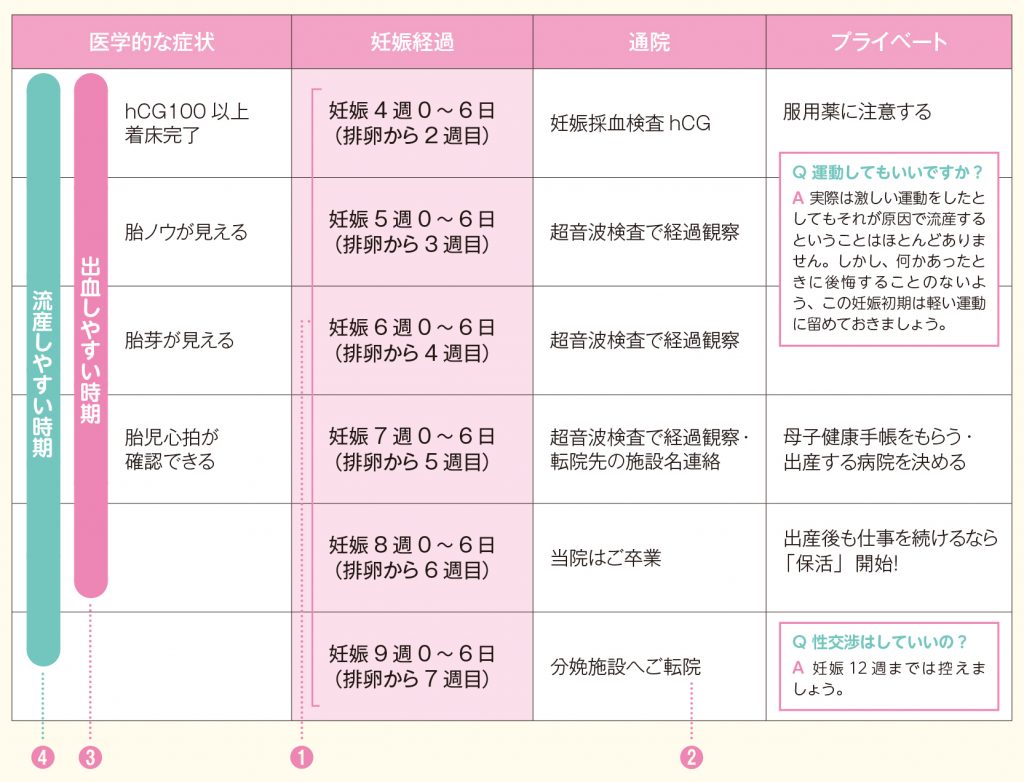

妊娠2カ月 妊娠4週 7週 ごろのお母さんの体調の変化 はぐふる

妊娠2カ月 妊娠4 7週 ベビーカレンダー

医療監修 妊娠2ヶ月目の妊婦と胎児の基礎知識 心拍確認の時期と生活での注意点 ママリ

妊娠初期 1 4か月 2か月 4 7週 妊娠期 育児期カレンダー まめコミ

妊娠2ヶ月 妊娠4週 5週 6週 7週 妊娠初期 のおなかの赤ちゃんの様子 妊娠 出産 育児に関する総合情報サイト ベビカム

医療監修 妊娠2ヶ月目の妊婦と胎児の基礎知識 心拍確認の時期と生活での注意点 ママリ

妊娠2カ月 妊娠4週 7週 ごろのお母さんの体調の変化 はぐふる

妊娠2か月目 妊娠4 7週の胎児の様子 母体の症状や気を付けること 妊娠初期 All About

妊娠2か月目 妊娠4 7週の胎児の様子 母体の症状や気を付けること 妊娠初期 All About

妊娠初期 1 4か月 2か月 4 7週 妊娠期 育児期カレンダー まめコミ

妊娠2ヶ月 妊娠4週 5週 6週 7週 の胎児と母体の状態 おむつのムーニー 公式 ユニ チャーム

妊娠2ヶ月 妊娠4週 5週 6週 7週 の胎児と母体の状態 おむつのムーニー 公式 ユニ チャーム